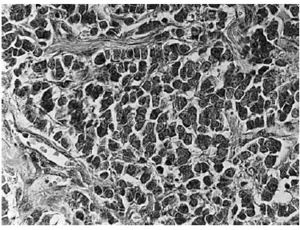

Se trata de un hombre de 87 años de edad con antecedentes de hipertensión arterial en tratamiento con nifedipino, carcinoma espinocelular de frente y adenocarcinoma de próstata, que entre los años 1996 y 1998 presentó cuatro lesiones diagnosticadas como LNH de tipo B en brazo, antebrazo, axila y párpado que fueron tratados quirúrgicamente sin objetivarse datos de recidiva durante su posterior seguimiento. En 1998 presentó en su nalga derecha un tumor redondeado de 3 cm de diámetro de bordes bien definidos y coloración eritematosa. Las tinciones con hematoxilina-eosina mostraban células pequeñas indiferenciadas agrupadas en láminas y trabéculas con frecuentes mitosis y núcleos hipercromáticos (fig. 2). Los estudios inmunohistoquímicos con cromogranina, sinaptofisina y citoqueratinas fueron positivos para CCM.

Fig. 2.--Caso 2. Células del tumor de Merkel.